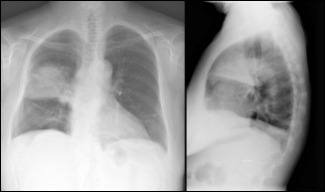

La neumonía sigue siendo la primera causa de muerte dentro de las enfermedades de causa infecciosa. Para evitar los tratamientos antibióticos de amplio espectro, y la consecuente aparición de resistencias, es importante diagnosticar el microorganismo responsable. El más...